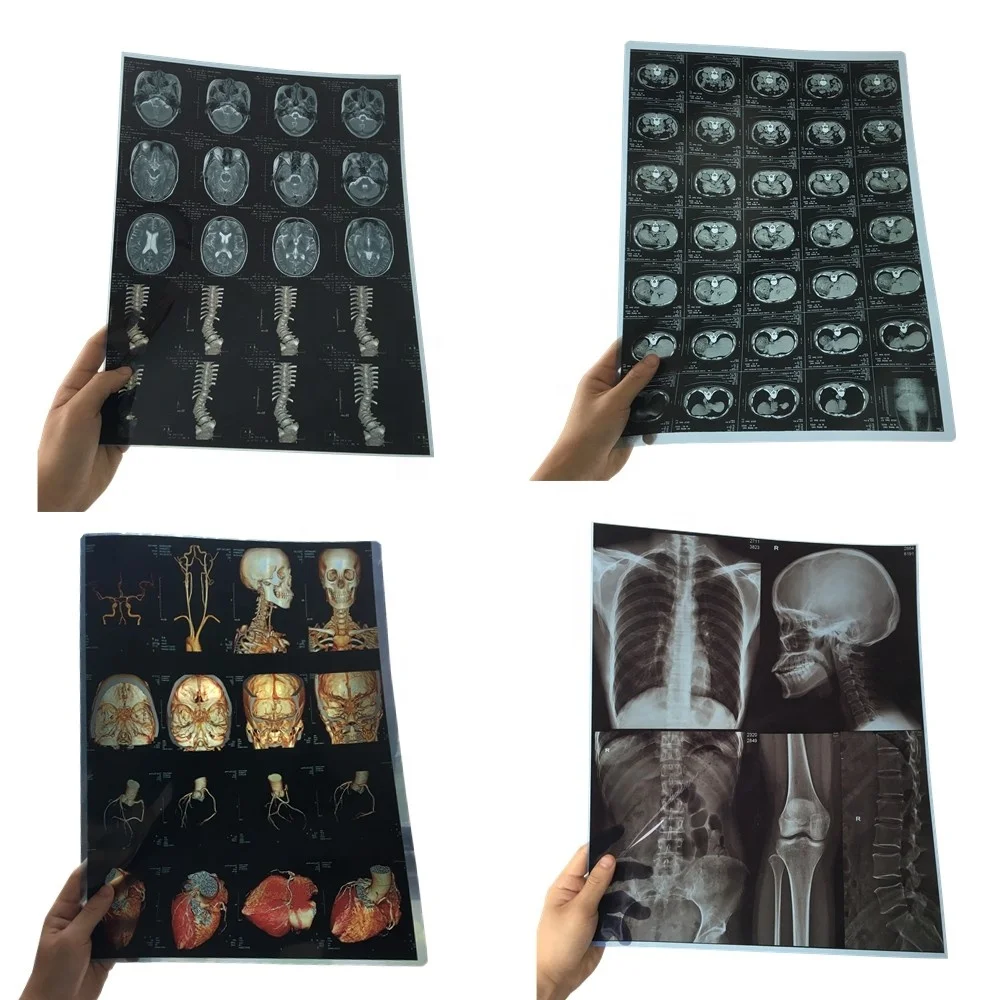

Лазерная камера для печати медицинских изображений на пленке стандарт dicom